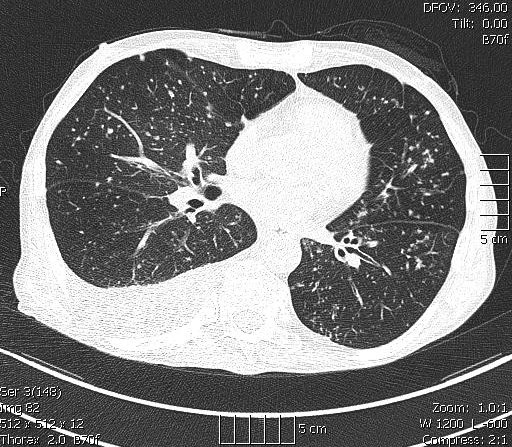

Miliáris gócok axiális CT felvételen